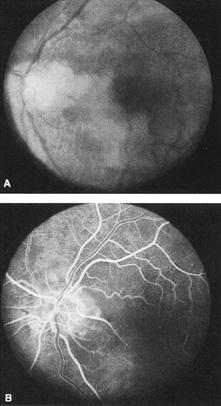

Ophthalmic artery obstruction is characterized by an initial opacification of the entire retina in a manner similar to that of central retinal artery obstruction (Fig. 4A). The cherry-red spot may or may not be present, however.119 The difference between an ophthalmic artery obstruction and central retinal artery obstruction is that in an ophthalmic artery obstruction, with time, optic atrophy develops, as does varying amounts of pigmentation due to the lack of perfusion of the retinal pigment epithelium (see Fig. 4D). This pigment is generally diffusely scattered throughout the posterior pole but it may also be seen in greater amounts in the periphery.

Intravenous fluorescein angiography generally shows moderate to marked abnormalities in the filling of the choroid, in addition to a delay in filling or even nonfilling of retinal vessels (see Fig. 4B and 4C). Staining of the retinal pigment epithelium can also be seen; this staining either can occur locally in the macular area or it can be diffuse.119 The electroretinogram shows abnormalities of both a- and b-waves, reflecting ischemia to both the inner and outer retina. Almost all reported patients have had an initial visual acuity of no light perception; virtually no patients can be expected to have a final visual acuity better than that.119 An acuity of no light perception is a clue to the presence of an ophthalmic artery obstruction. Because relatively few patients with central retinal artery obstruction have an initial visual acuity of no light perception, no light perception usually suggests the likelihood of some obstruction of the choroidal circulation.14